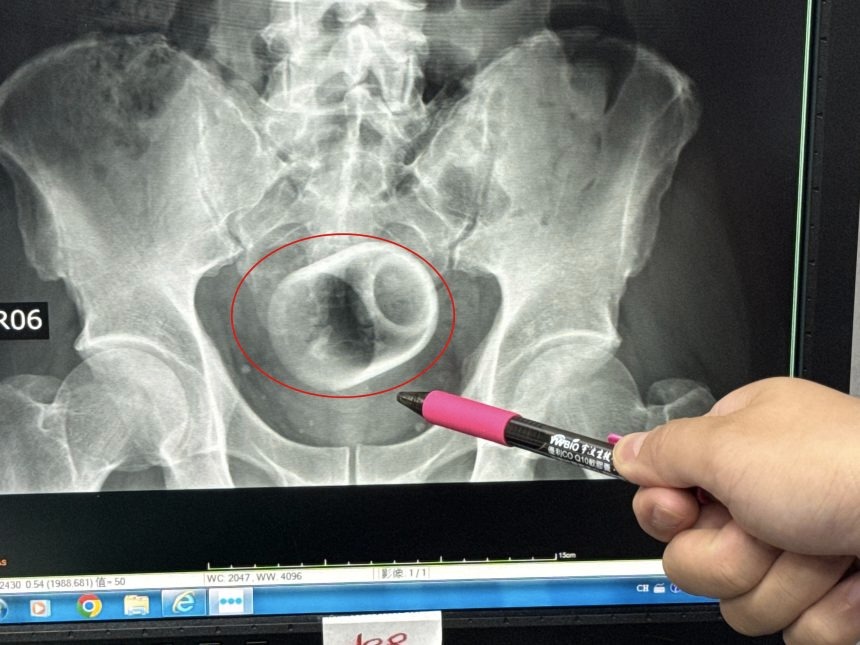

Doctors in Taiwan have removed a ceramic teacup from a man’s rectum after he arrived at the hospital complaining of severe abdominal pain.

The patient reported being unable to pass stool for three days, accompanied by intense abdominal pain and bloating. An X-ray revealed a ceramic teacup lodged upside down inside his rectum.

Dr. Wu added that he was shocked when he first saw the X-ray.